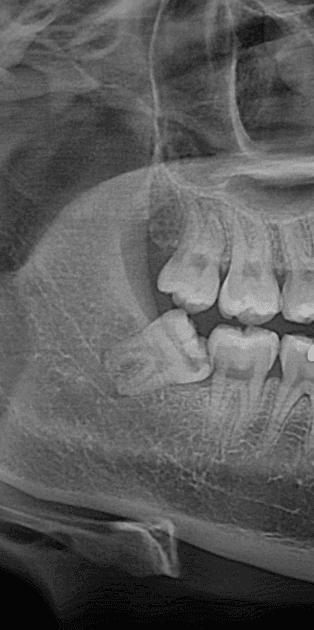

반면 뼈 안에 완전히 파묻혀 있는 사랑니는 이야기가 다릅니다.

잇몸을 절개하고, 이를 조각조각 나눠서 빼내야 하기 때문에 진동도 크고 시술 시간도 길어집니다.

## 누워 있는 사랑니는 왜 더 어렵게 빠지나요?

그런데 사랑니가 옆으로 누워 있으면 나올 방향 자체가 막혀 있습니다. 그대로는 빠질 수가 없는 구조입니다.

그래서 이를 잘라서 일부를 꺼내고, 또 잘라서 꺼내는 방식을 반복해야 합니다.

발치 전 X-ray와 상담을 통해 본인의 사랑니가 어떤 상태인지 먼저 확인하고, 그에 맞는 마취 방법을 선택하시는 것이 가장 현명한 방법입니다.